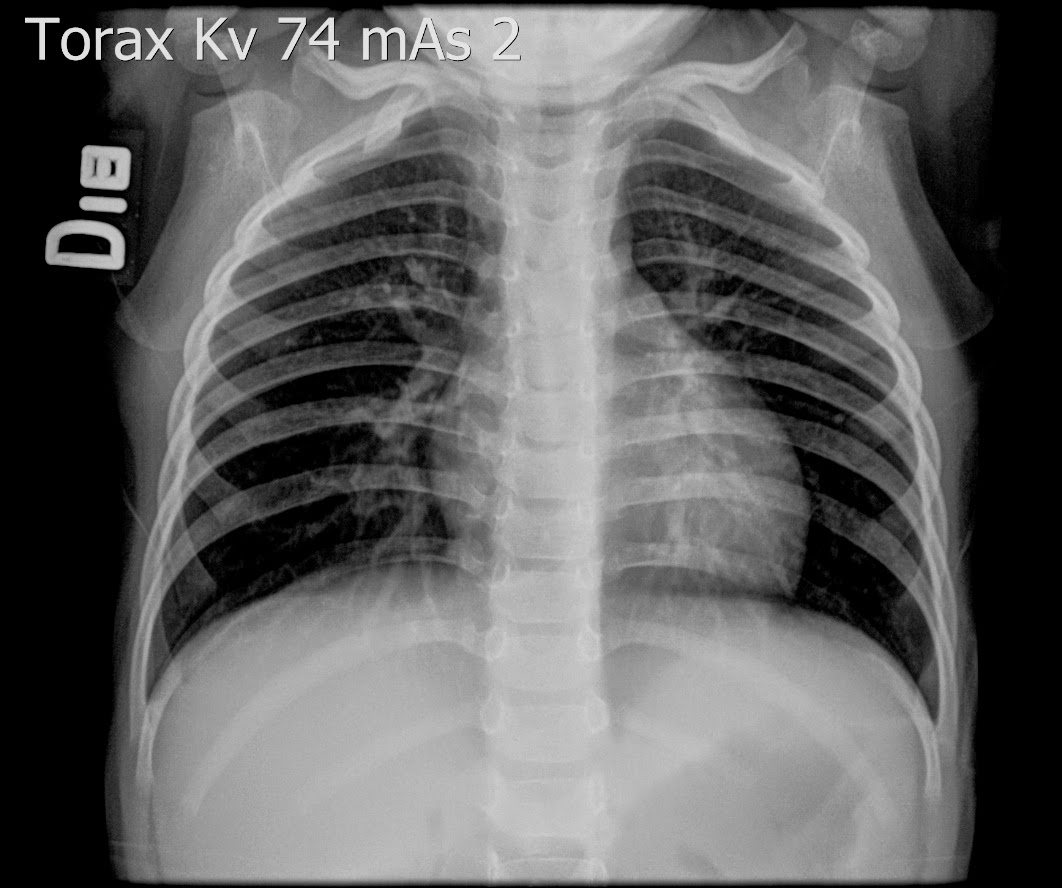

Caso interesante #2

¿A QUE CORRESPONDE Y PORQUE SE PRODUCE ESTA IMAGEN

IMÁGENES RADIOLÚCIDAS BILATERALES EN FORMA DE LUNA MENGUANTE ADYACENTE A LAS CABEZAS HUMERALES??????